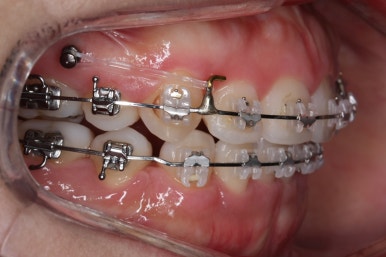

점점 개선이 되고 있는 모습이 보입니다.

정면으로 맞물렸던 교합도 좋아지고 있으며 이로 인해 자연스레 위아래의 앞뒤 간격도 맞닿게 되고 좁아지고 있습니다.

좌측에서 본 모습도 마찬가지입니다.

발치 후에 남아있던 미세한 공간도 없어졌고 윗니도 후방 이동 되면서 교합이 좋아지고 있습니다.

윗니를 봐도 미세하게 남았던 발치를 했던 공간이 없어졌습니다.

마무리 후에 다시 벌어질 수 있는 틈을 유지장치를 붙여 놓았습니다.